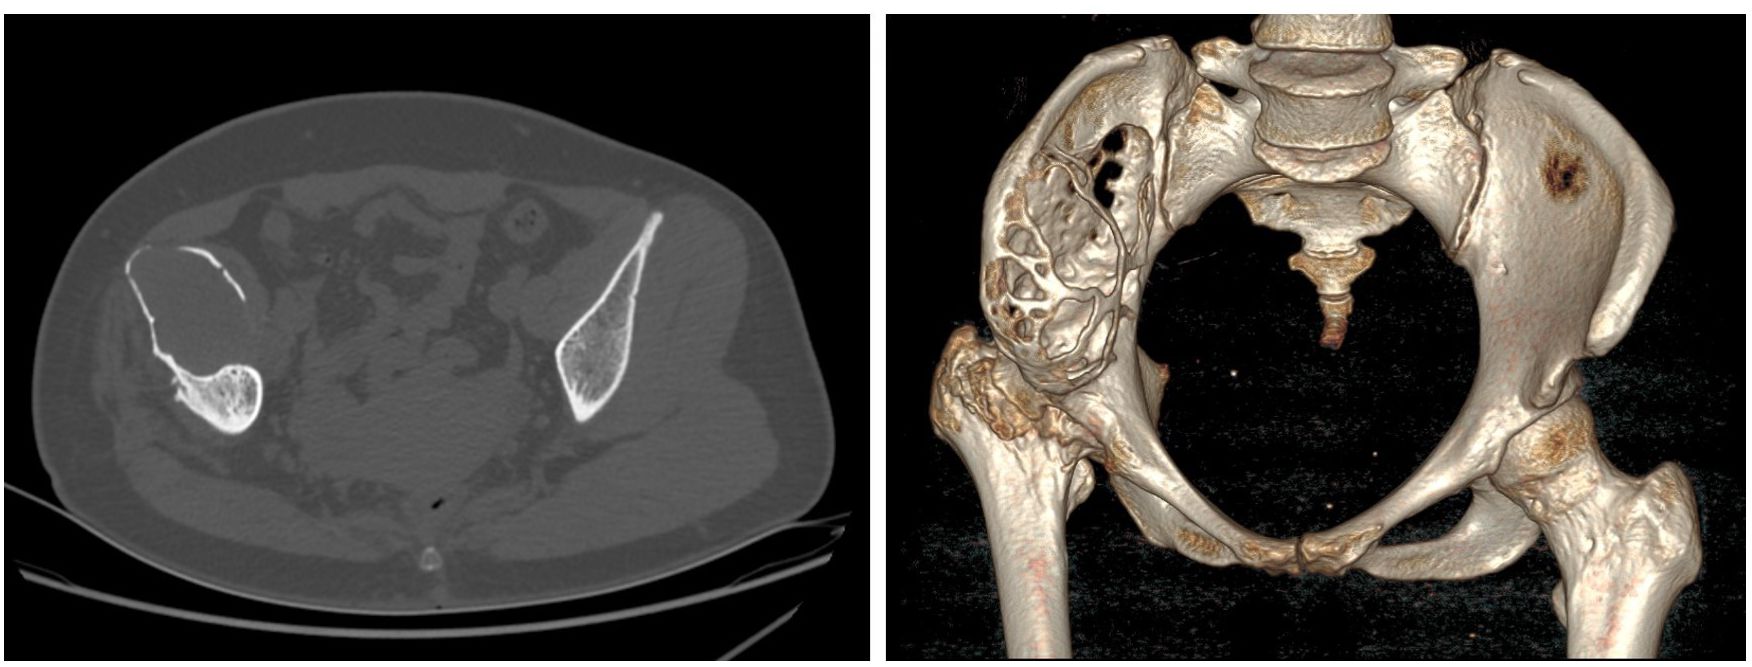

Laboratory examinations revealed no significant abnormalities. The pelvic plain film showed that the joint space of the right hip joint was narrowed, the femoral neck was shortened, and there was ischemic necrosis of the femoral head. Radiographs revealed a large expansile radiolucent lesion, with cortical erosion of the right iliac bone (Figure 1). Computed tomography (CT) revealed significant osteolytic destruction in the right iliac wing, along with a mass in the surrounding tissue. Irregular cystic degeneration areas were observed within it. The mass, measuring approximately 10.3 cm × 6.2 cm × 7.8 cm, had an indistinct boundary with muscle tissue (Figure 2). Magnetic resonance imaging (MRI) revealed an iliac mass showing hypo intensity.

Figure 1

Figure 1. The pelvic plain film showed a narrowed joint space of the right hip joint, a shortened femoral neck, and ischemic necrosis of the femoral head. Also, radiographs revealed a large expansile radiolucent lesion with cortical erosion in the right iliac bone. 左: left.